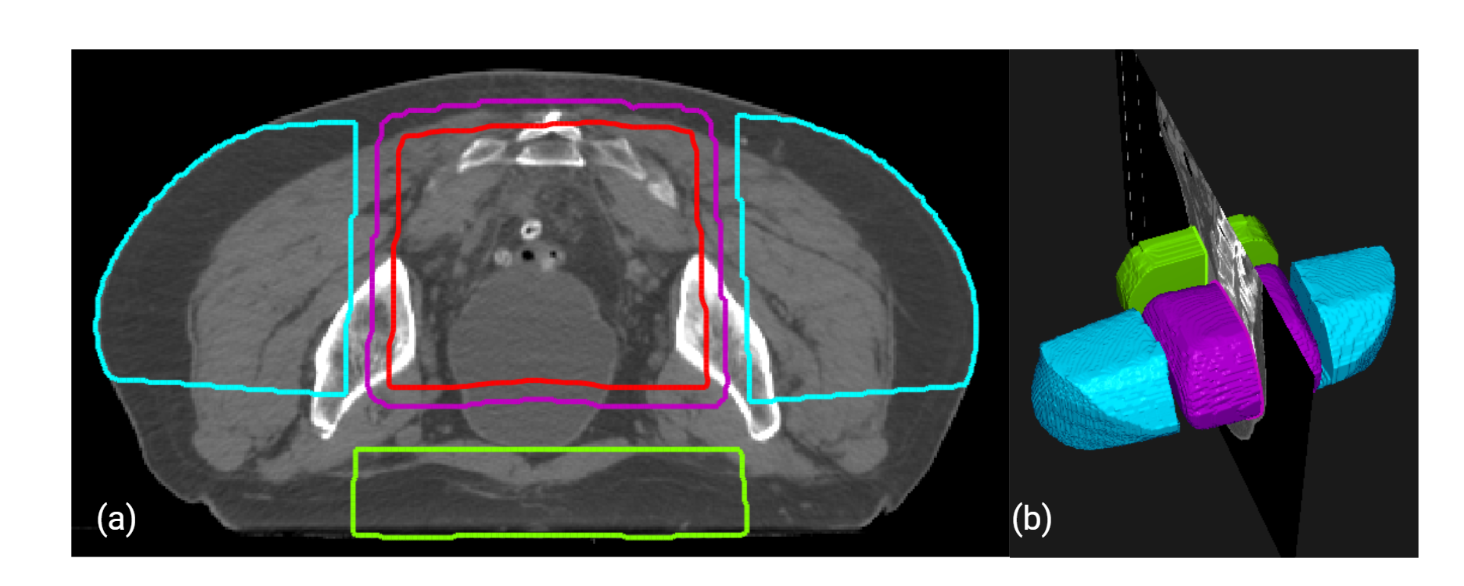

Figure 4: The figure shows an example of the constructed volumes for the experimental setup. The purple volume is the region of high dose, the red volume is pseudo-region of interest (ROI), the blue volumes are LTRT, and the green volume shows APPA. Part (a) shows a transverse slice, and (b) shows a three-dimensional view of the volumes.

In this study, we independently evaluated the performance of the FIF program by retrospectively testing the program on 20 patients using clinical apertures with 3-field geometry without boost fields. The following structures were constructed by ROI algebra. The region of high dose (RHD) is the volume overlap of primary beams. RHD is used to penalize hotspots. PTV is not contoured before the FIF algorithm is run; therefore, the program constructs a pseudo-ROI (pROI) by uniformly eroding the RHD by 1 cm.To achieve dose objectives for regions, including femur and bowel space without having to create accurate contours,two structures named LTRT and APPA were introduced. LTRT structures are the two regions on the lateral sides of the PTV, formed by the overlap of the lateral beams minus the 1-cm expansion of RHD.Finally,APPA is the region on the anterior side of the PTV, formed by the overlap of the AP and PA beams minus the 1-cm expansion of RHD. As there is no AP beam in the 3-field geometry, only the PA beam is used to construct APPA. Figure 4 shows an example of the aforementioned volumes.